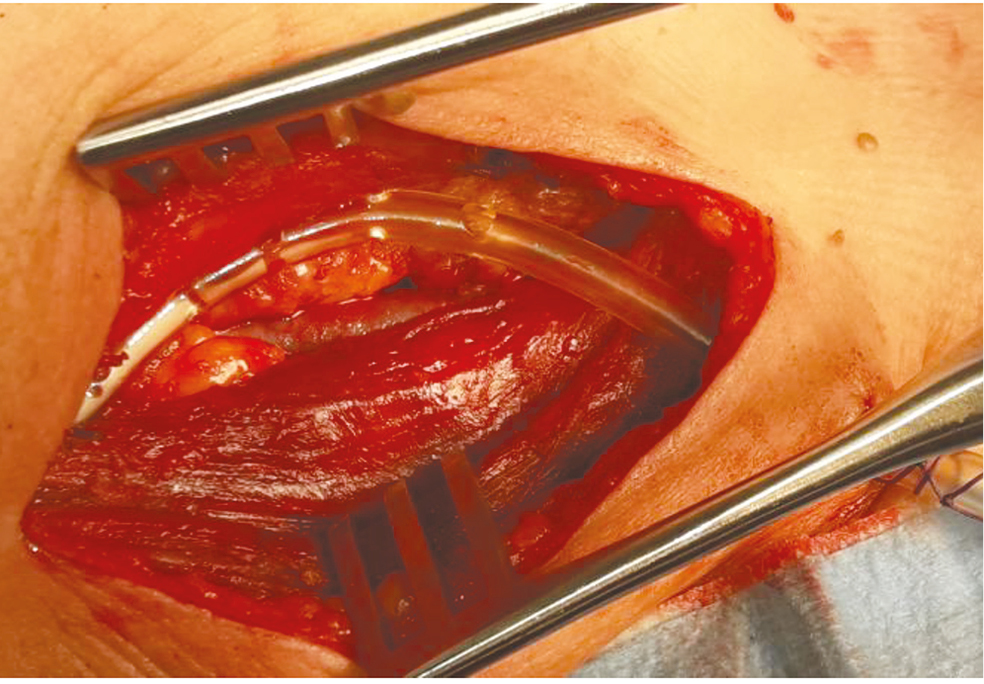

С 2012–2017 гг. проведено 84 гибридных операции ЧКВ+ классическая КЭЭ с пластикой артерии заплатой из диэпоксиобработанного ксеноперикарда. На первом этапе больной поступал в рентген-операционную, где ему выполнялось ЧКВ, во время которого внутриартериально вводилось 10 000 ЕД гепарина. Далее в течение получаса пациент транспортировался в сосудистую операционную, где ему выполнялась КЭЭ, во время которой вводилось еще 5000 ЕД гепарина. После завершения операции и экстубации он получал нагрузочную дозу клопидогреля 600 мг перорально. До 2015 г. гемостаз и дренирование раны после КЭЭ нами выполнялись следующим образом. Паравазальное пространство коагулировалось электрокоагуляцией. Ушивались ткани между внутренней яремной веной (ВЯВ) и сонными артериями, образуя футляр над артерией. Сверху укладывался дренаж, и производилось послойное ушивание раны. В рамках настоящей работы эти больные (n = 38) вошли в 1-ю группу. После 2015 г. методика гемостаза была изменена. После завершения основного этапа операции рана тампонируется на 5 мин. Затем тампон извлекается и производится укутывание артерии гемостатической губкой «Тахокомб» или «Серджисел» (Takeda Austria GmbH, Австрия) (рис. 1).

Рис. 1. Укутывание артерии гемостатической губкой «Тахокомб»

Fig. 1. Haemostatic sponge “Tachocomb” wrapping of artery

Это позволяет остановить диффузное кровотечение по ходу шва. Далее в это пространство укладывается первый дренаж (рис. 2).